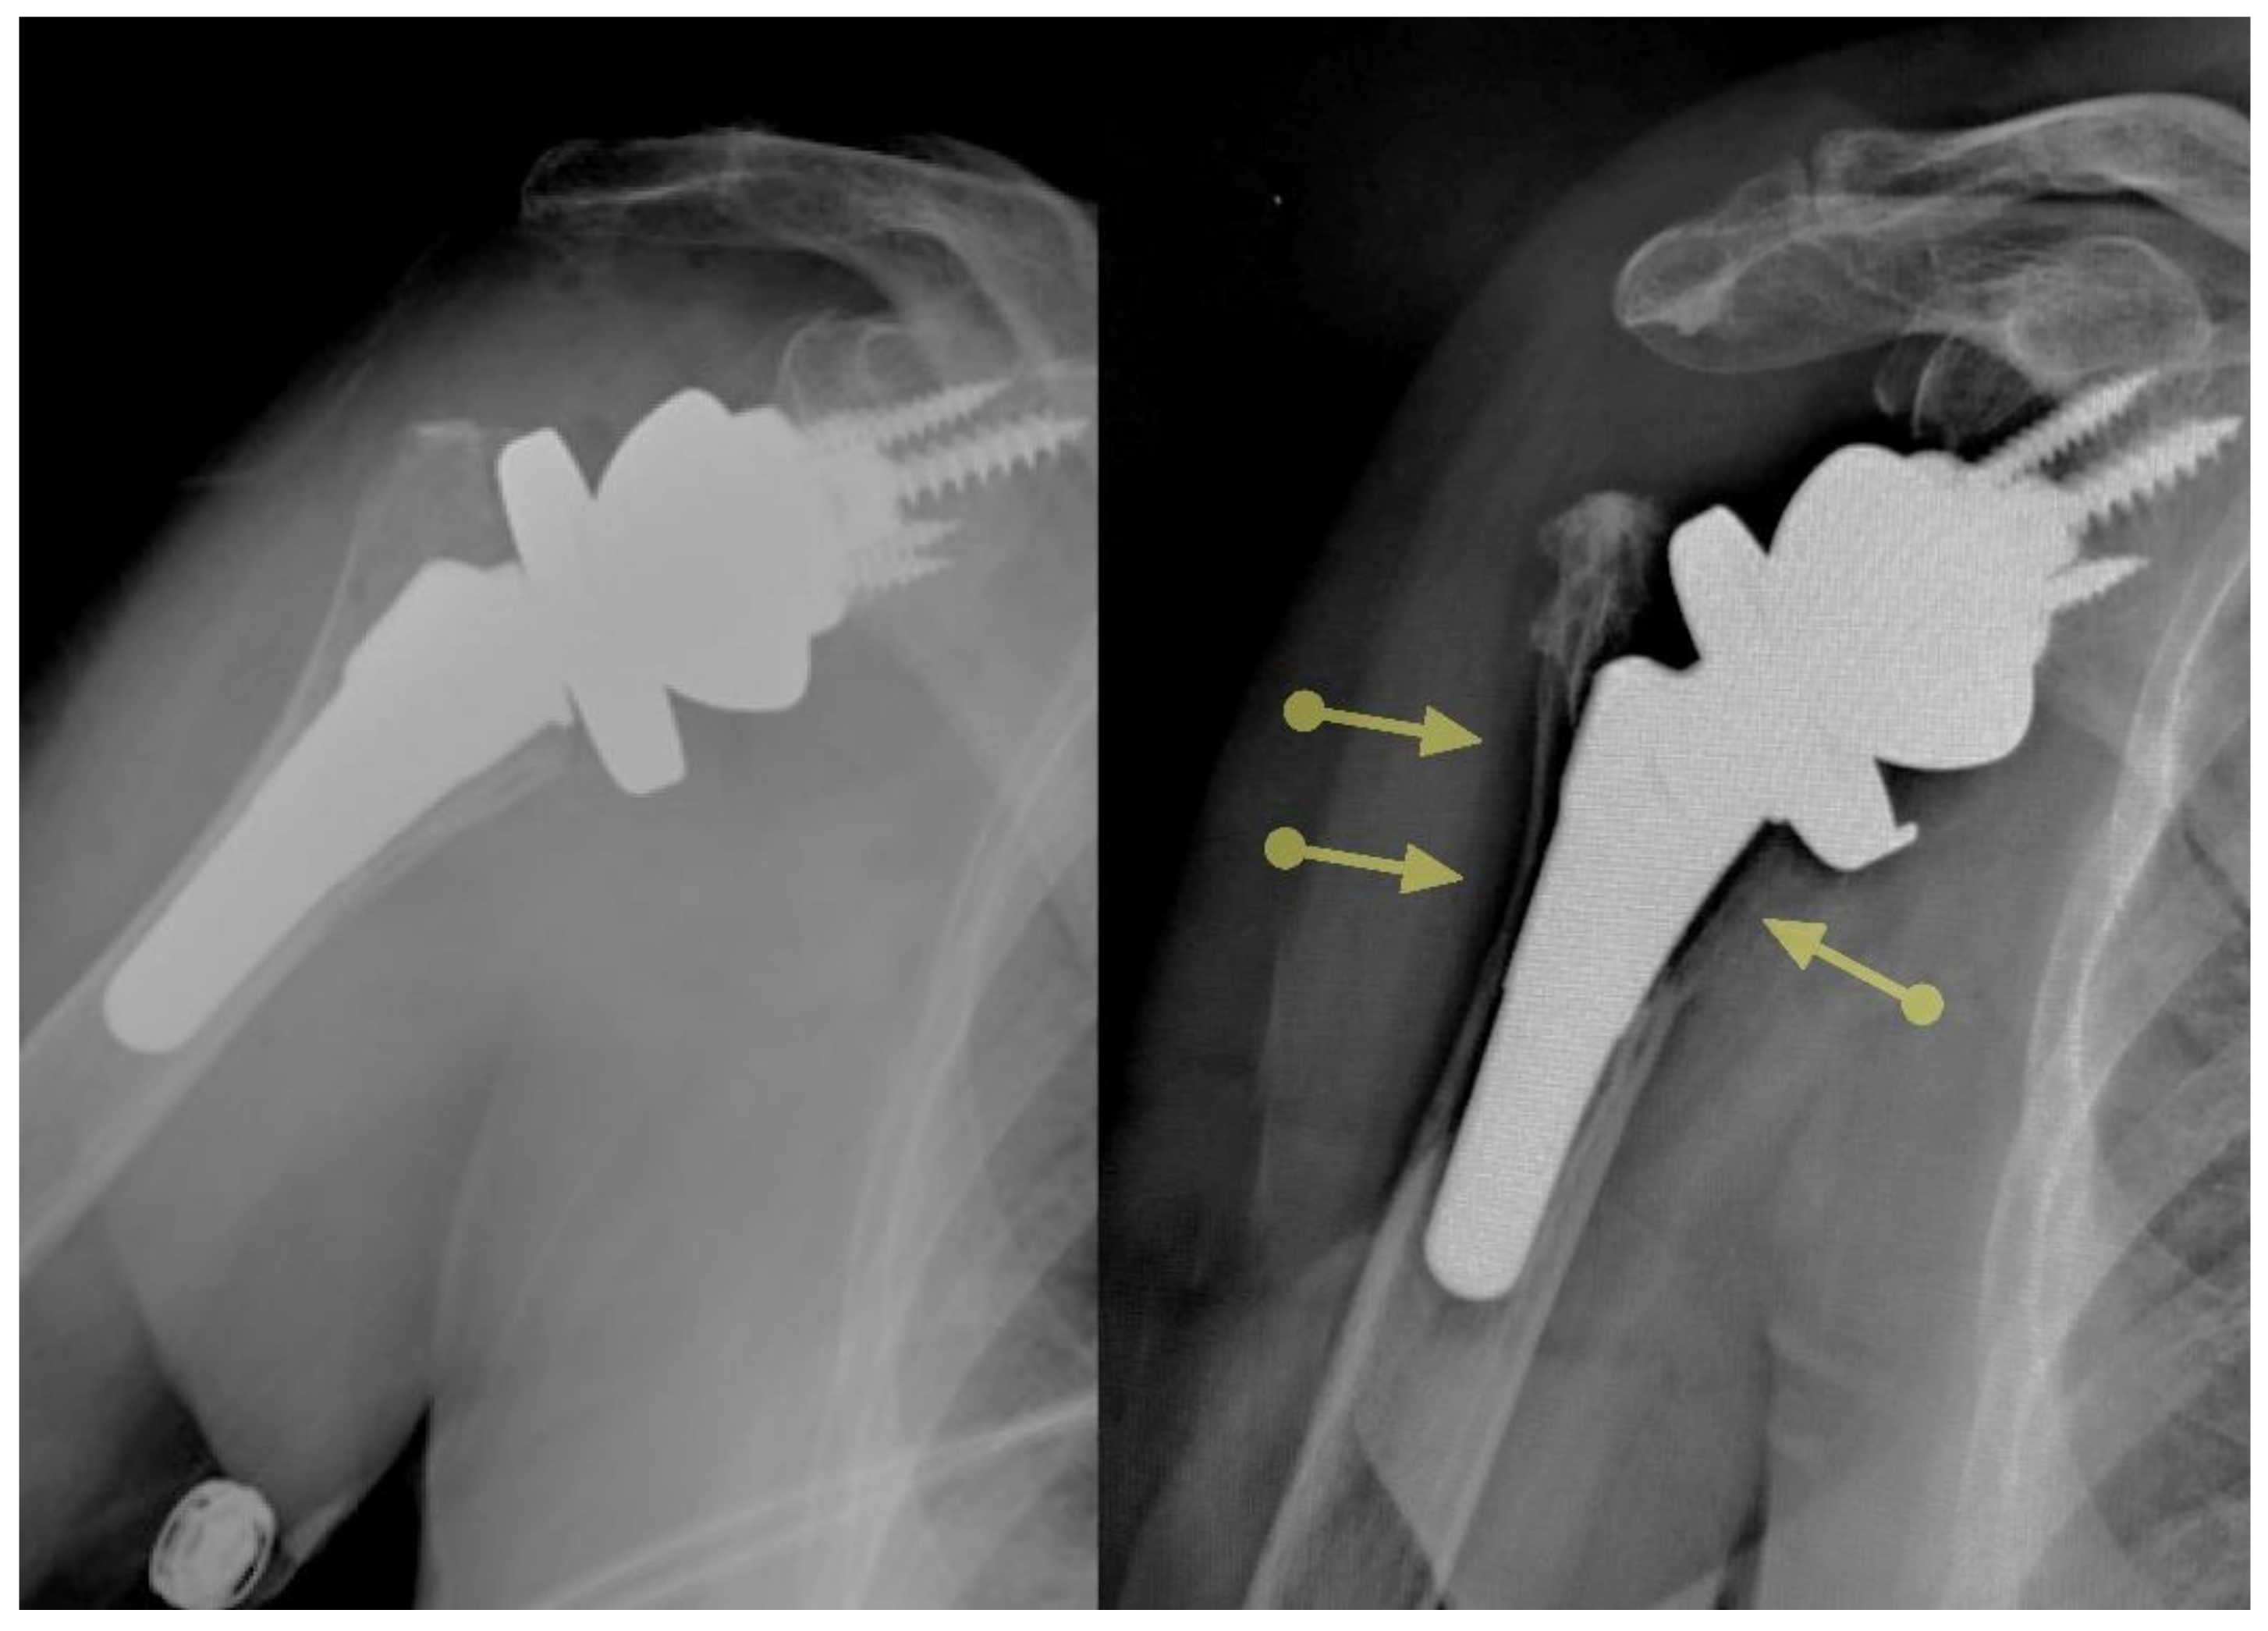

However, the onlay vs. inlay controversy should probably be abandoned for two reasons. Firstly, there is a high level of variability regarding how much lateralization and distalization are provided by the many implants in the market [25]. Classifying them as onlays or inlays is an oversimplification. What matters is where the humerus “lands” for a specific glenoid reconstruction, depending on the humeral implant selected and where it is implanted. This will affect the length and the moment arm of the deltoid and rotator cuffs [26]. Secondly, surgeons may implant inlay components in an onlay fashion or the other way around. For example, the original prosthesis designed by Dr. Frankle was an inlay design; however, its proximal portion was relatively large and could not be fully inset in the humeral metaphysis of many patients, thus resulting in an onlay application of an inlay design (Figure 5). By the same token, if thicker polyethylene bearings or a metal spacer are added to an inlay prosthesis to guarantee adequate stability, the pivot point is at an onlay level despite the implant being designed as an inlay. Consequently, even though implants that allow placement of the pivot point at or below the cut surface of the humerus are necessary to optimize soft tissue tension across the whole spectrum of shoulder replacements, in many shoulders, these inlay components will behave as onlay ones because thicker polyethylenes may be needed to avoid dislocation, especially in the cuff-deficient shoulder. The ideal degree of humeral lateralization probably varies from individual to individual depending on the underlying diagnosis and other characteristics.

Figure 5.

This implant was designed as an inlay, but its large size resulted in an onlay application most of the time.